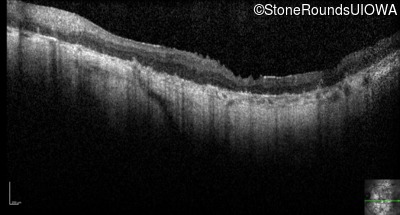

Optical Coherence Tomography - Left - Hand Motion

Exemplar / OCT Stack